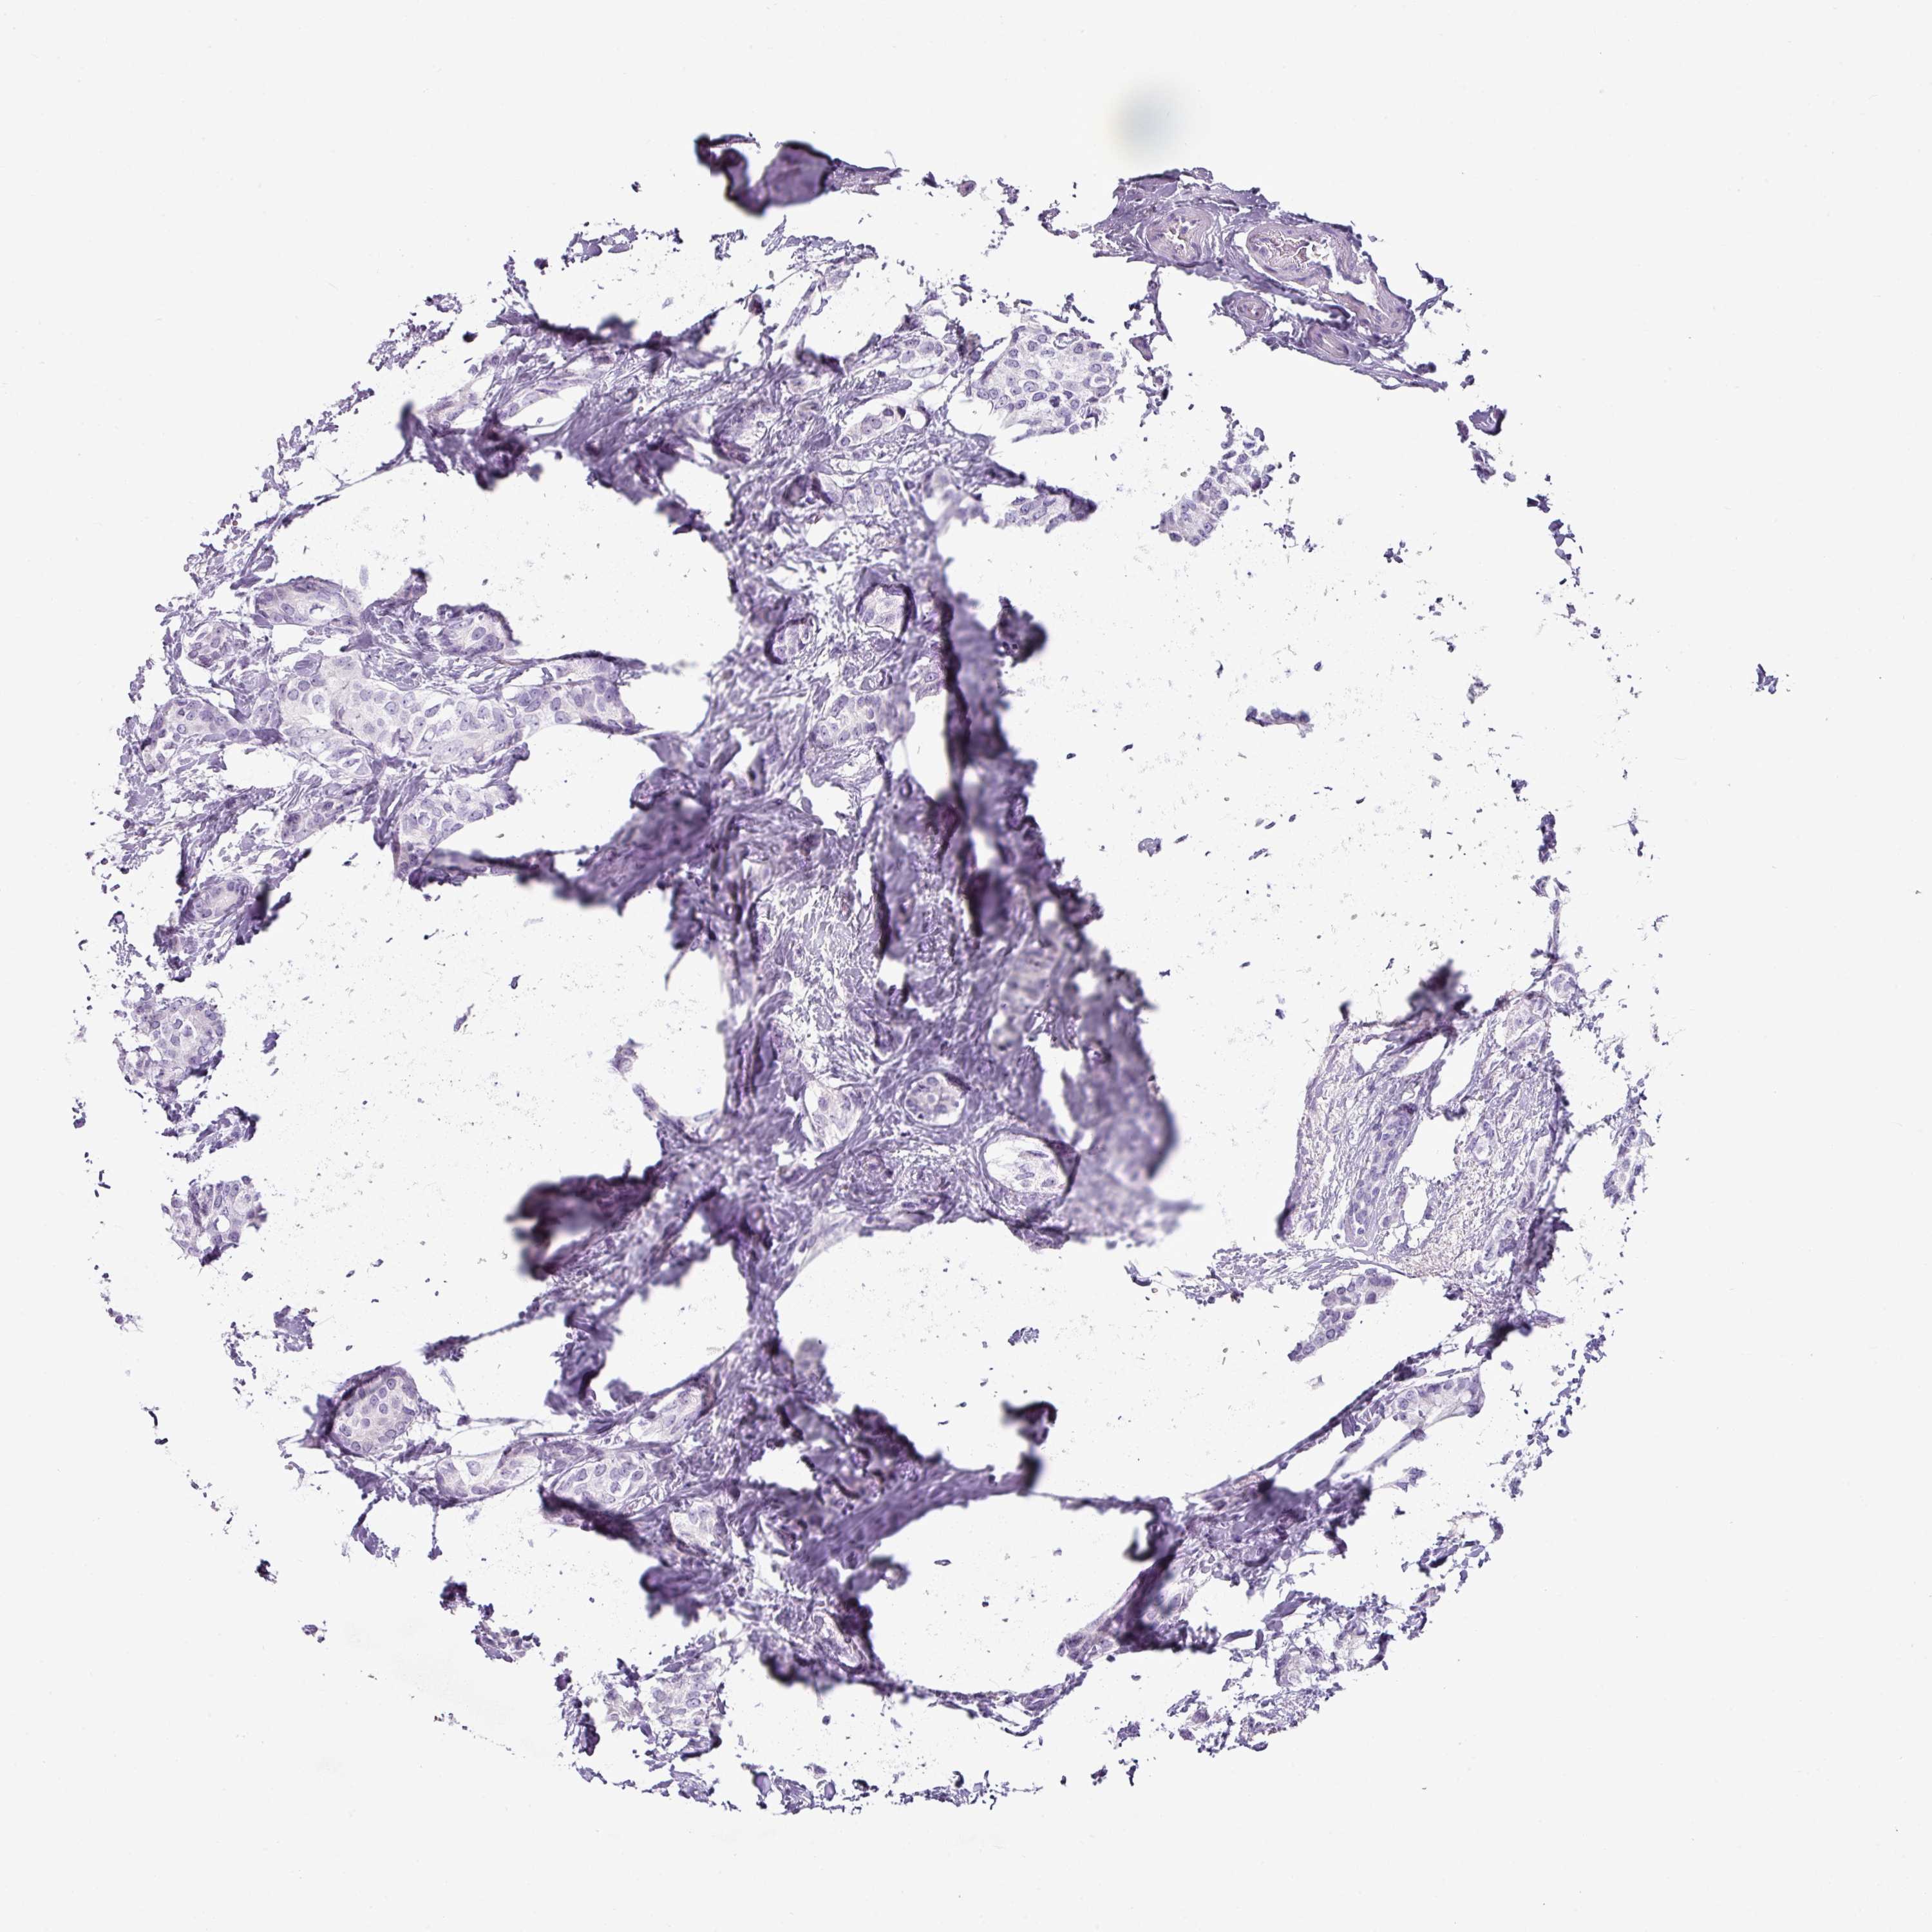

CANCER BREAST CANCER Show tissue menu

Breast cancer

Human cancer